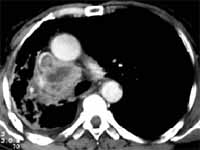

Figura 10. Carcinoma escamolecular asociado a pérdida de volumen y compromiso pleural.

Tiene una gran importancia en el estudio de las características de las lesiones nodulares, en los que estudios han demostrado que ciertos tipos morfológicos han sido relacionados en un mayor porcentaje con benignidad (calcificación central, calcificación laminada, patrón de roseta de maíz). Así como su tamaño, menores de 3 cms (4,28), así como las malignas se relacionan en un mayor porcentaje con lesiones mal definidas, espiculadas, pseudocavitadas, etc.) (4,28).